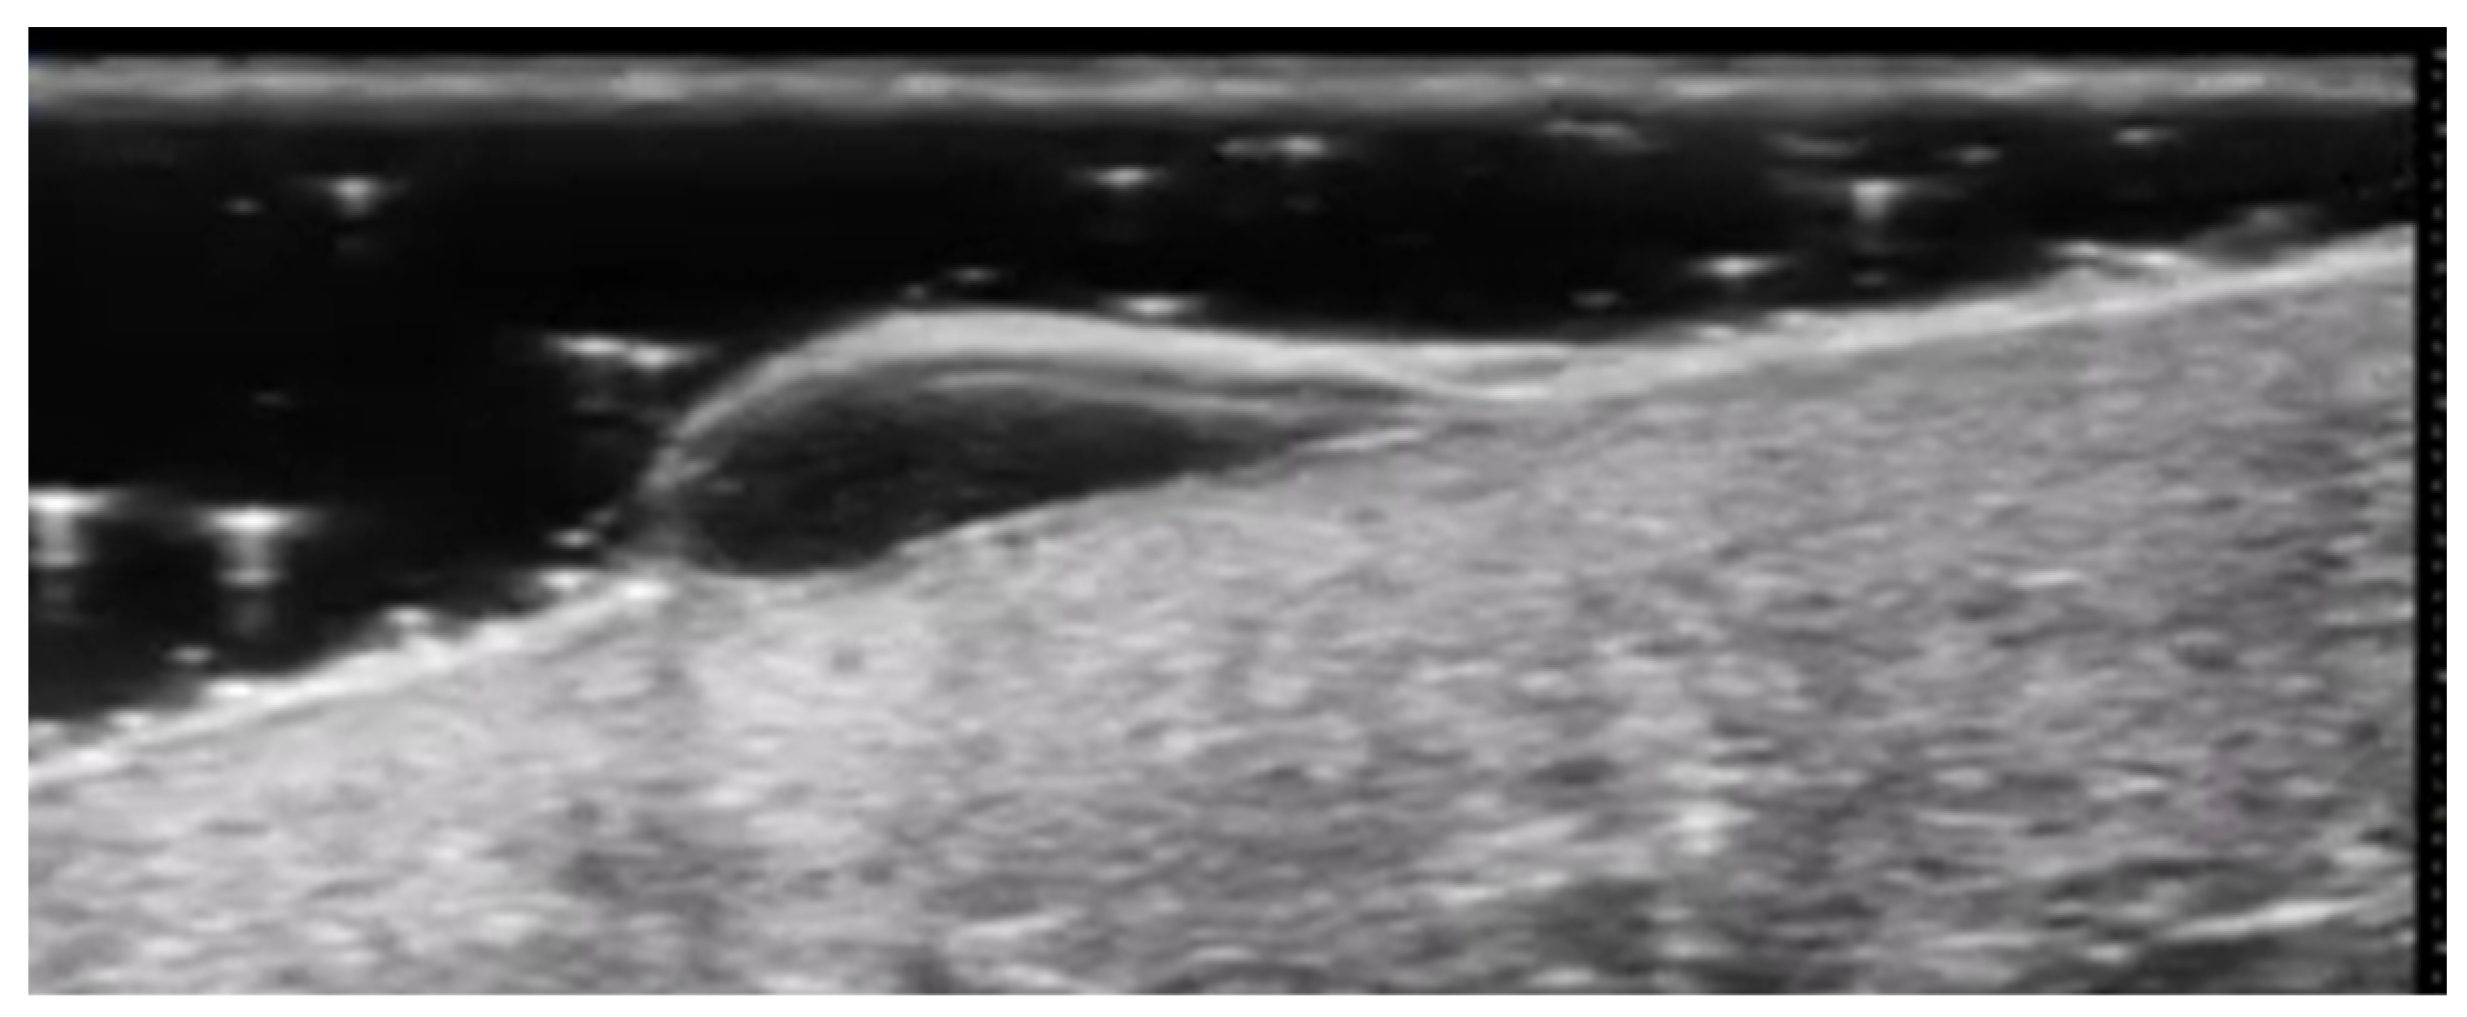

5. Specific Cutaneous Structure and Sites of Skin Disorders

4. Metabolic and Genetic Disorders